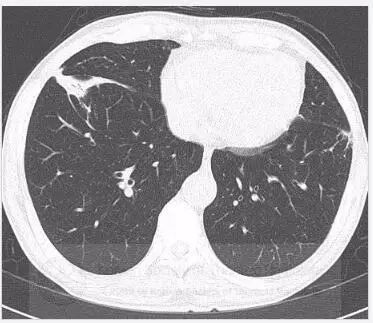

初始胸片显示双肺斑片状或外周实变,以及磨玻璃影。胸部CT显示双肺多灶性、斑片状实变,伴中央空气支气管征,以及外周磨玻璃影。病变在外周、上叶多见。

鉴别诊断:包括慢性嗜酸粒细胞性肺炎、隐源机化性肺炎和Churg-Strauss综合征。

诊断:慢性嗜酸粒细胞性肺炎